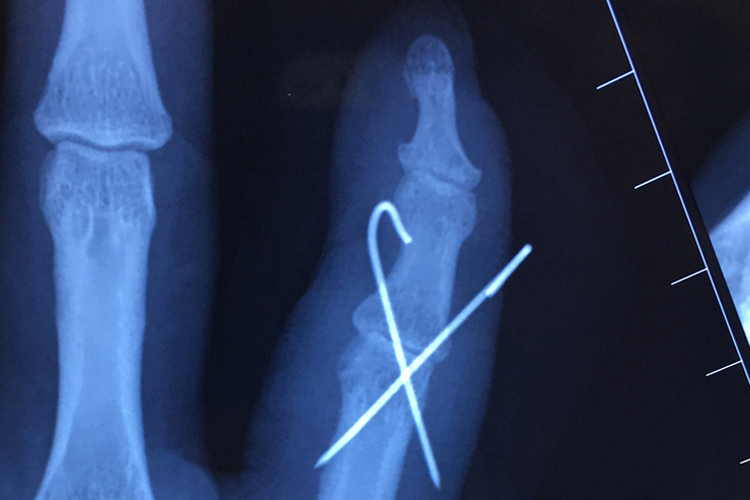

小手指错位通常指关节脱位,表现为局部肿胀、疼痛,X光片可见指骨脱离原有关节,可通过手法复位后固定,恢复正常关节形态。

小手指错位通常为小指关节脱位,可通过手法复位后进行固定,并配合药物治疗,以促进恢复。恢复过程中需通过X光片确认关节和两侧骨骼位置的恢复情况,最初可见关节明显脱位,两侧指骨不对应;固定时可见关节两侧骨骼恢复正常位置;恢复后可见关节两侧骨骼在去除固定后,仍然维持正常位置,关节形态恢复正常。